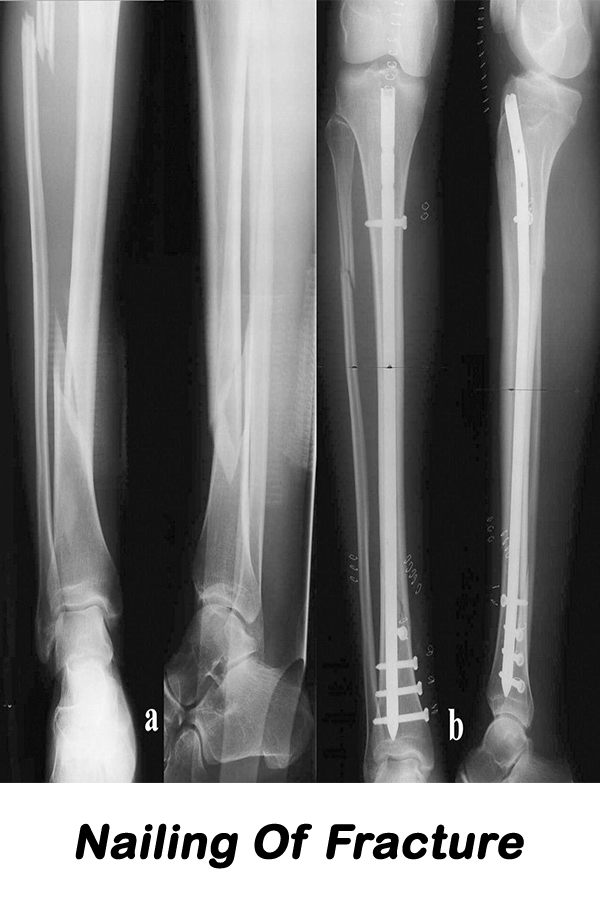

Shreerang Hospital is orthopaedic specialty hospital and is designed specifically for the orthopedic patient. Such a specialized facility and team of experts means we have the utmost in experience and understanding of the needs of orthopaedic patients meaning better outcomes, increased patient satisfaction and a reduced risk of infection or complications. Our goal is to provide you with the ultimate patient experience and excellent outcomes when undergoing orthopaedic surgery. Your care, comfort & peace of mind is constantly our top priority from pre-admission through your surgery & stay at our hospital.

Be the best place for orthopaedic & surgical, Provide quality and accessible orthopaedic & surgical services with the latest technology & equipments.

Our objective to maintain high standards of orthopaedic & surgical treatment, care and surgery. The main objective of the hospital is to offer high quality and more prominent patient care.